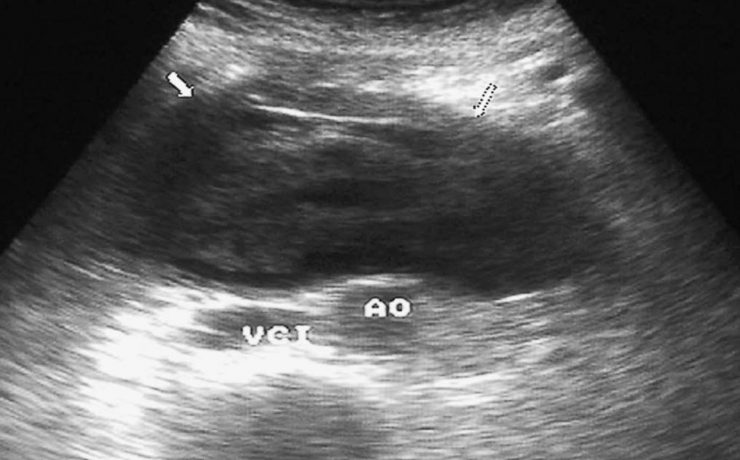

Nódulo de tiroides

La glándula tiroides es con frecuencia afectada por diferentes patologías de tipo funcional y orgánico, que conllevan a cambios funcionales y estructurales de este órgano. Cuando estos cambios son estudiados por medios radiográficos, arrojan una serie de imágenes características que contribuyen con una de las funciones médicos sociales más importantes,